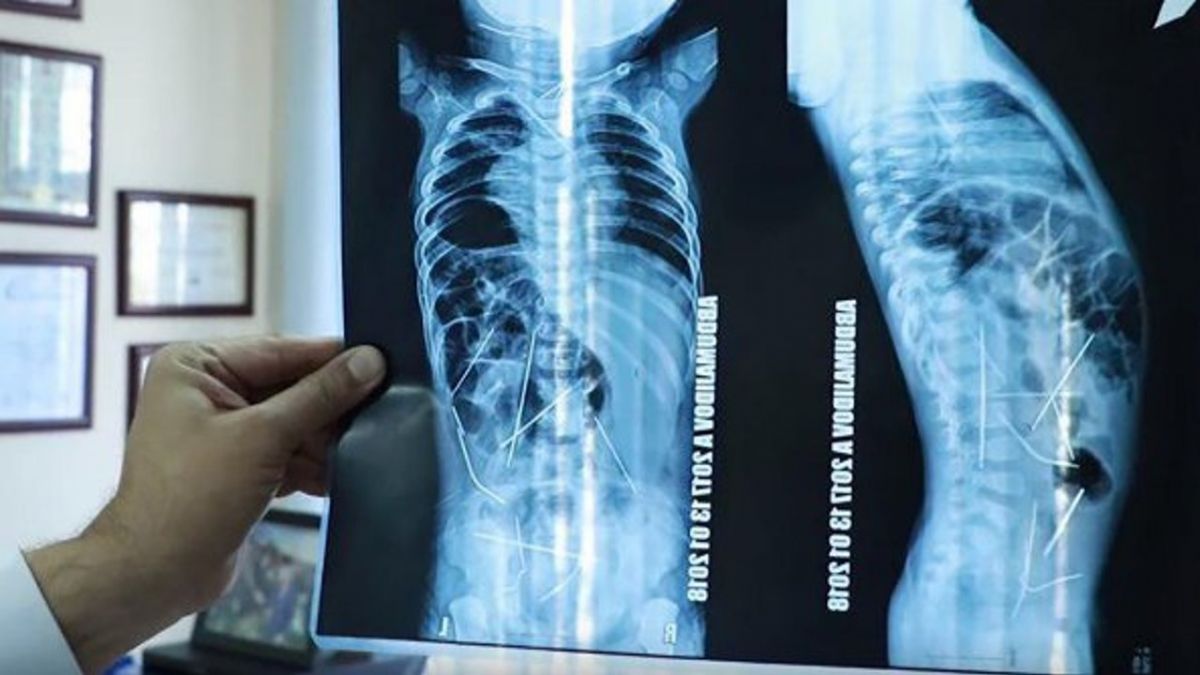

中亞烏茲別克近日傳出一起駭人聽聞的虐童事件!一位母親見11個月大的兒子高燒不退,而且排尿不順,急忙前去醫院求診,醫生原本以為是肺炎,沒想到X光一照,驚見男嬰體內插有多根金屬長針,有些刺在腸道、膀胱等部位中,還有一些靠近心臟,X光畫面直叫人頭皮發麻,而且醫生認定,這麼小的孩童根本不可能自行吞食長針,顯然是有人凌虐所致。

綜合外媒報導,經過9小時的開刀手術,醫師順利將男嬰體內的10根針移除,其中9根從腹部,1根從頸部,另外由心臟外科醫師,將男嬰胸腔內靠近心臟的3根取出,仍有3根針在男嬰內,預計在下一次的手術中取出,所幸男嬰目前狀況穩定。

目前醫生還不了解究竟針是怎麼進入男嬰體內,不過很顯然,只有11個月大的男嬰不可能會自己吞針,因此認定針是被人扎進體內,根據研判,這些針已經在男嬰體內存有1個月之久。